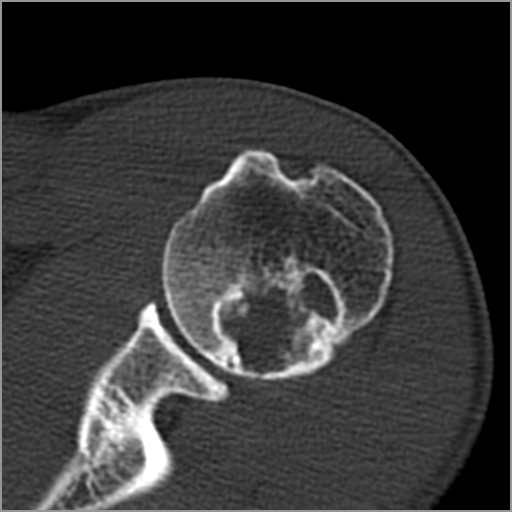

以下是引用zxd95在2008-7-19 18:45:00的发言:[br]囊性病灶边缘硬化、皮质变薄但连续——提示生长时间长、良性病变——考虑左肱骨头骨囊肿。[br]

以下是引用杀毒软件在2008-7-19 18:55:00的发言:[br]考虑:骨巨细胞瘤可能性大